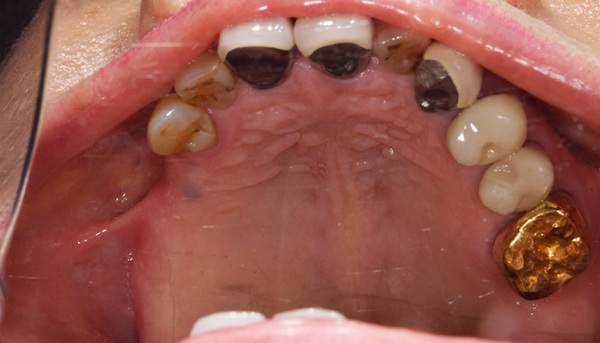

ケース2(自費の総入れ歯と部分入れ歯)

上下の入れ歯が外れやすくなったということでいらっしゃいました。 顎の骨はしっかりしていましたので、精密な型取りさえすればしっかりした入れ歯がつくれると思いました。 また下には6本歯が残っていましたが、虫歯になっている歯もありました。 かぶせ物のなかで大きな虫歯があった歯があり、1本だけ残せない状態でした。

上の入れ歯は確かに吸着は甘くなっていました。 また下の入れ歯はバネの一部が壊れており、安定感がなくなっていました。

精密な型取りの後、噛み合わせのチェックをしていきました。 かぶせ物も同時に作っていきました。

歯を並べた後、かぶせ物のフレーム作ってもらいました。先に歯を並べて理想の位置を決めておくことが大切です。

完成した入れ歯とかぶせ物です。 入れ歯への寛容度が高い患者様でしたので、 金属は使用せず、プラスチックのみで上は仕上げました。 下顎も歯は1本減ってしまいましたが、しっかり 入れ歯が維持できる様な構造にしました。

お口の中に入れた状態です。 見た目も最初とほとんど変わることなく作成できました。 維持や吸着に関しても問題ないようでした。

年齢 80歳・女性

主訴 上下の入れ歯が外れやすくなった

治療期間 3ヶ月

治療費 .メタルボンドクラウン:550,000円

.義歯:990,000円(税込、上下)

治療方針 長年使ってきた義歯の人工歯が磨耗し、臼歯部での咬合がすくなくなり、入れ歯の安定も悪くなり、あたりどころが悪くなって痛みが出ている。 そのため、入れ歯を上下作りかえる必要がある。

治療内容 過去に治療を行ったことのある歯が再度虫歯になってしまっているところがあり、すでに残せない状態にまでなっていたため、歯を一本抜歯した。 その後、かぶせ物と入れ歯を同時に作成していった。

特記事項 歯を抜いた後は、2〜3ヶ月歯ぐきの回復を待ってから入れ歯を作るため、待機期間があります。その間、古い入れ歯を調整しながらそのまま使うか、新し物をつくっておく必要があります。ただし、入れ歯は保険治療で作成する場合、6ヶ月は新しいものが作れないという決まりがあるので保険で全て作りたい場合は注意が必要です。